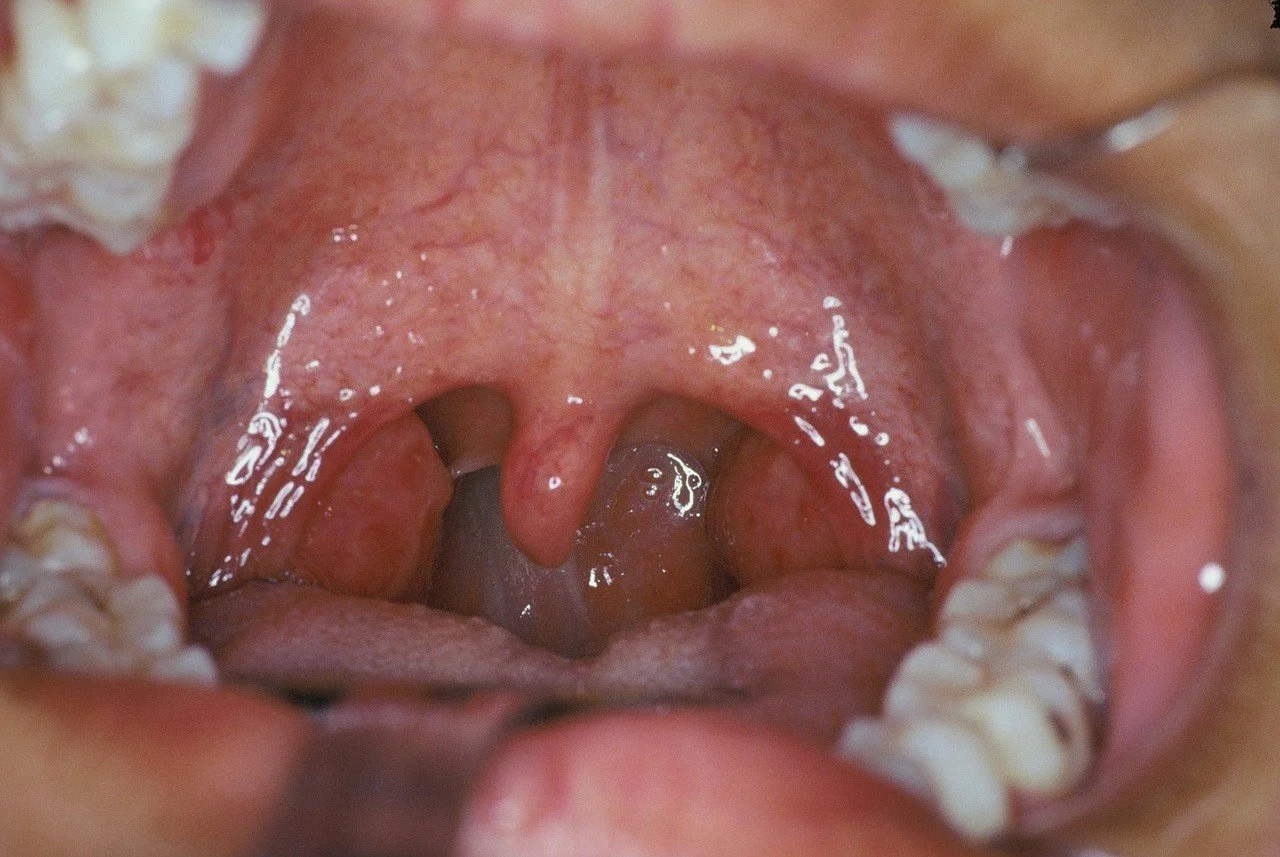

Hypertrophic tonsils are common causes of upper airway obstruction causing sleep apnea and snoring.

Tonsiller Enlargement causing Upper Airway Obstruction & Snoring

Obstructive Tonsillar Lesion.

Adenotonsiller hyperplasia is a common cause for snoring and obstructive sleep apnea in children.

This can be resolved easily by an adenotonsillectomy.